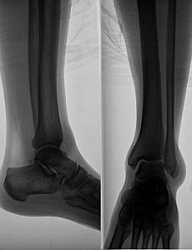

Akútny dnový zápal kĺbu je hlavným znakom klinickej dny. Jeho vznik sa spája s viacerými provokujúcimi faktormi, akými sú nadmerné požitie alkoholu a nevhodných potravín, chirurgický výkon, úraz, krvácanie, infekcia a podávanie niektorých liekov. Veľmi bolestivý zápal postihne najčastejšie kĺbové spojenie palca nohy s nohou, menej často členok, koleno, drobné kĺby rúk, zápästia a lakeť. Už Thomas Sydenham v 17. storočí popísal, že záchvat začína z plného zdravia okolo 2. hodiny v noci.

Postihnutý kĺb sčervenie, je teplý až horúci, lesklý, nápadne citlivý na dotyk a tlak, veľmi bolestivý pri pohybe. Chorý je vyčerpaný, potí sa a máva zvýšenú teplotu. Akútny zápal môže trvať niekoľko dní až týždňov. U väčšiny chorých sa ďalší atak objaví do jedného roku. Nasledujúce záchvaty môžu postihovať viacero kĺbov a ústup príznakov nie je už nikdy úplný. Vyvíja sa chronické štádium choroby s tvorbou dnových uzlíkov, ktoré sa usadzujú najmä v kĺboch a vedú k ich deštrukcii s následnými deformitami. Iná lokalizácia uzlíkov môže byť v podkoží, menej často v obličkách.